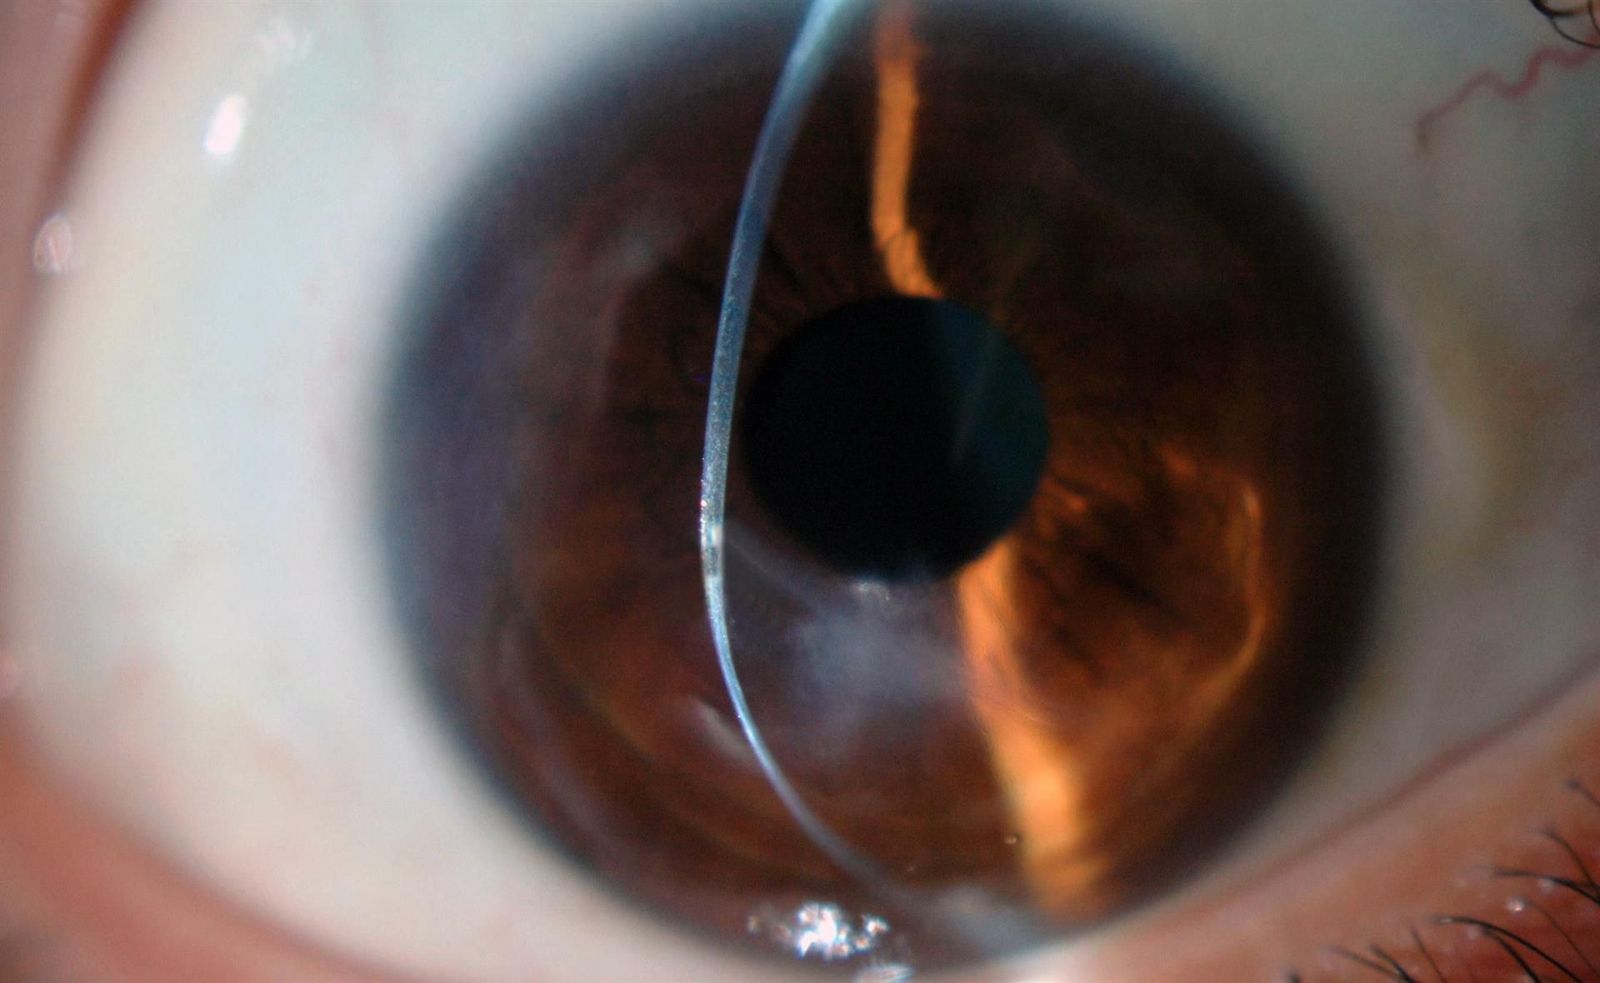

Archivo - Queratocono. EP

El catedrático de Oftalmología e investigador de Honor de la Universidad Miguel Hernández (UMH) de Elche, el profesor Jorge Alió, ha advertido de que el queratocono, una patología poco conocida que debilita progresivamente la córnea, es la causa más frecuente de transplante de córnea en menores de 40 años, todo ello de cara al día mundial de esta enfermedad, que se conmemora este domingo.

El queratocono se asocia a una deformación en forma de cono y su impacto es mayor en la cuenca mediterránea por su clima templado y floración frecuente y abundante, y su evolución empeora en áreas cálidas debido al frotamiento de los ojos causado por alergias, cuya frecuencia también es mayor en el mar Mediterráneo.